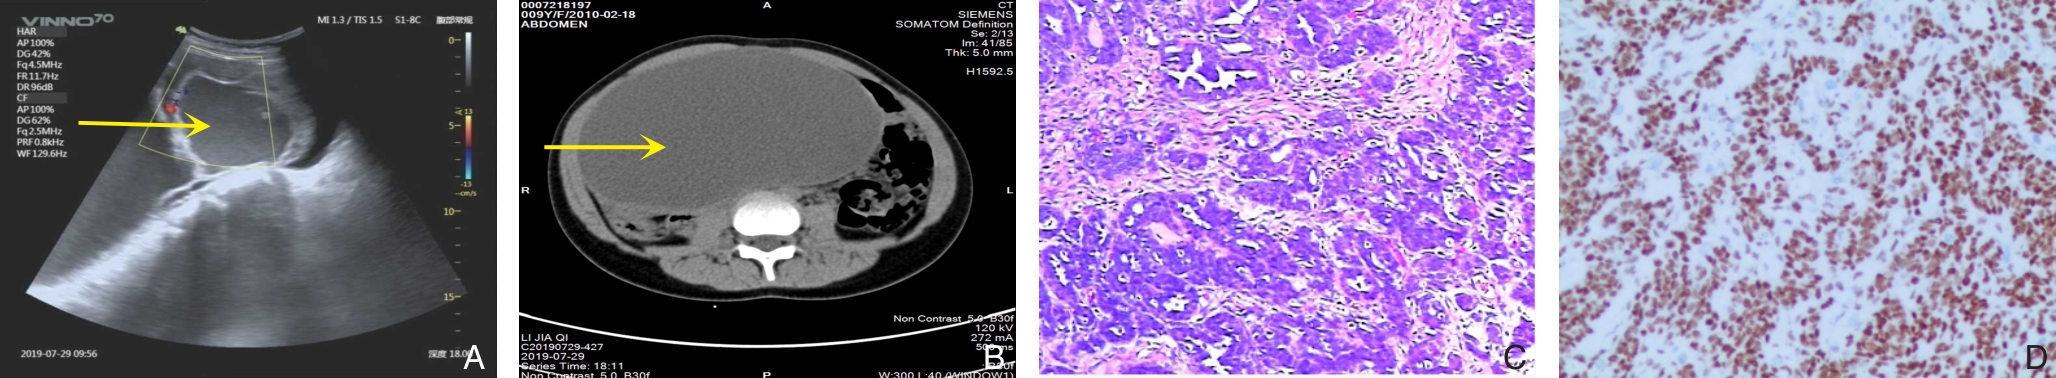

Background and Aims Hepatocellular carcinoma (HCC) presenting initially with bone metastasis is uncommon, and metastasis to the appendicular skeleton is particularly rare. These cases often lack typical liver disease history, elevated alpha-fetoprotein (AFP), or characteristic imaging findings, leading to frequent misdiagnosis or delayed diagnosis. This study reports a rare case of occult HCC presenting with humeral metastasis and reviews the literature to improve clinical recognition and management.Methods The clinical data of a 42-year-old male patient presenting with humeral metastasis as the initial manifestation admitted in August 2025 were retrospectively analyzed, including laboratory tests, multimodal imaging findings, histopathological and immunohistochemical results, treatment, and follow-up outcomes. Relevant literature was also reviewed.Results The patient presented with left shoulder pain. Imaging revealed osteolytic destruction of the left humerus. PET/CT incidentally detected multiple hepatic lesions without significant FDG uptake. Contrast-enhanced ultrasound demonstrated atypical enhancement patterns, initially suggesting a perivascular epithelioid cell tumor. Histopathological and immunohistochemical examination of biopsy specimens from both the humeral and hepatic lesions confirmed moderately differentiated hepatocellular carcinoma with humeral metastasis (CNLC stage IIIb). The patient received systemic therapy with sintilimab plus bevacizumab, followed by transcatheter arterial chemoembolization. After 6 months of follow-up, the intrahepatic lesions had decreased in size, the bone metastasis remained stable, and pain symptoms were significantly relieved.Conclusion HCC presenting with humeral metastasis as the initial manifestation is extremely rare and may lack typical imaging and serological features. Clinicians should consider HCC in patients with unexplained bone metastasis even in the absence of liver disease history or elevated AFP. Multimodal imaging and pathological biopsy are essential for accurate diagnosis and appropriate management.